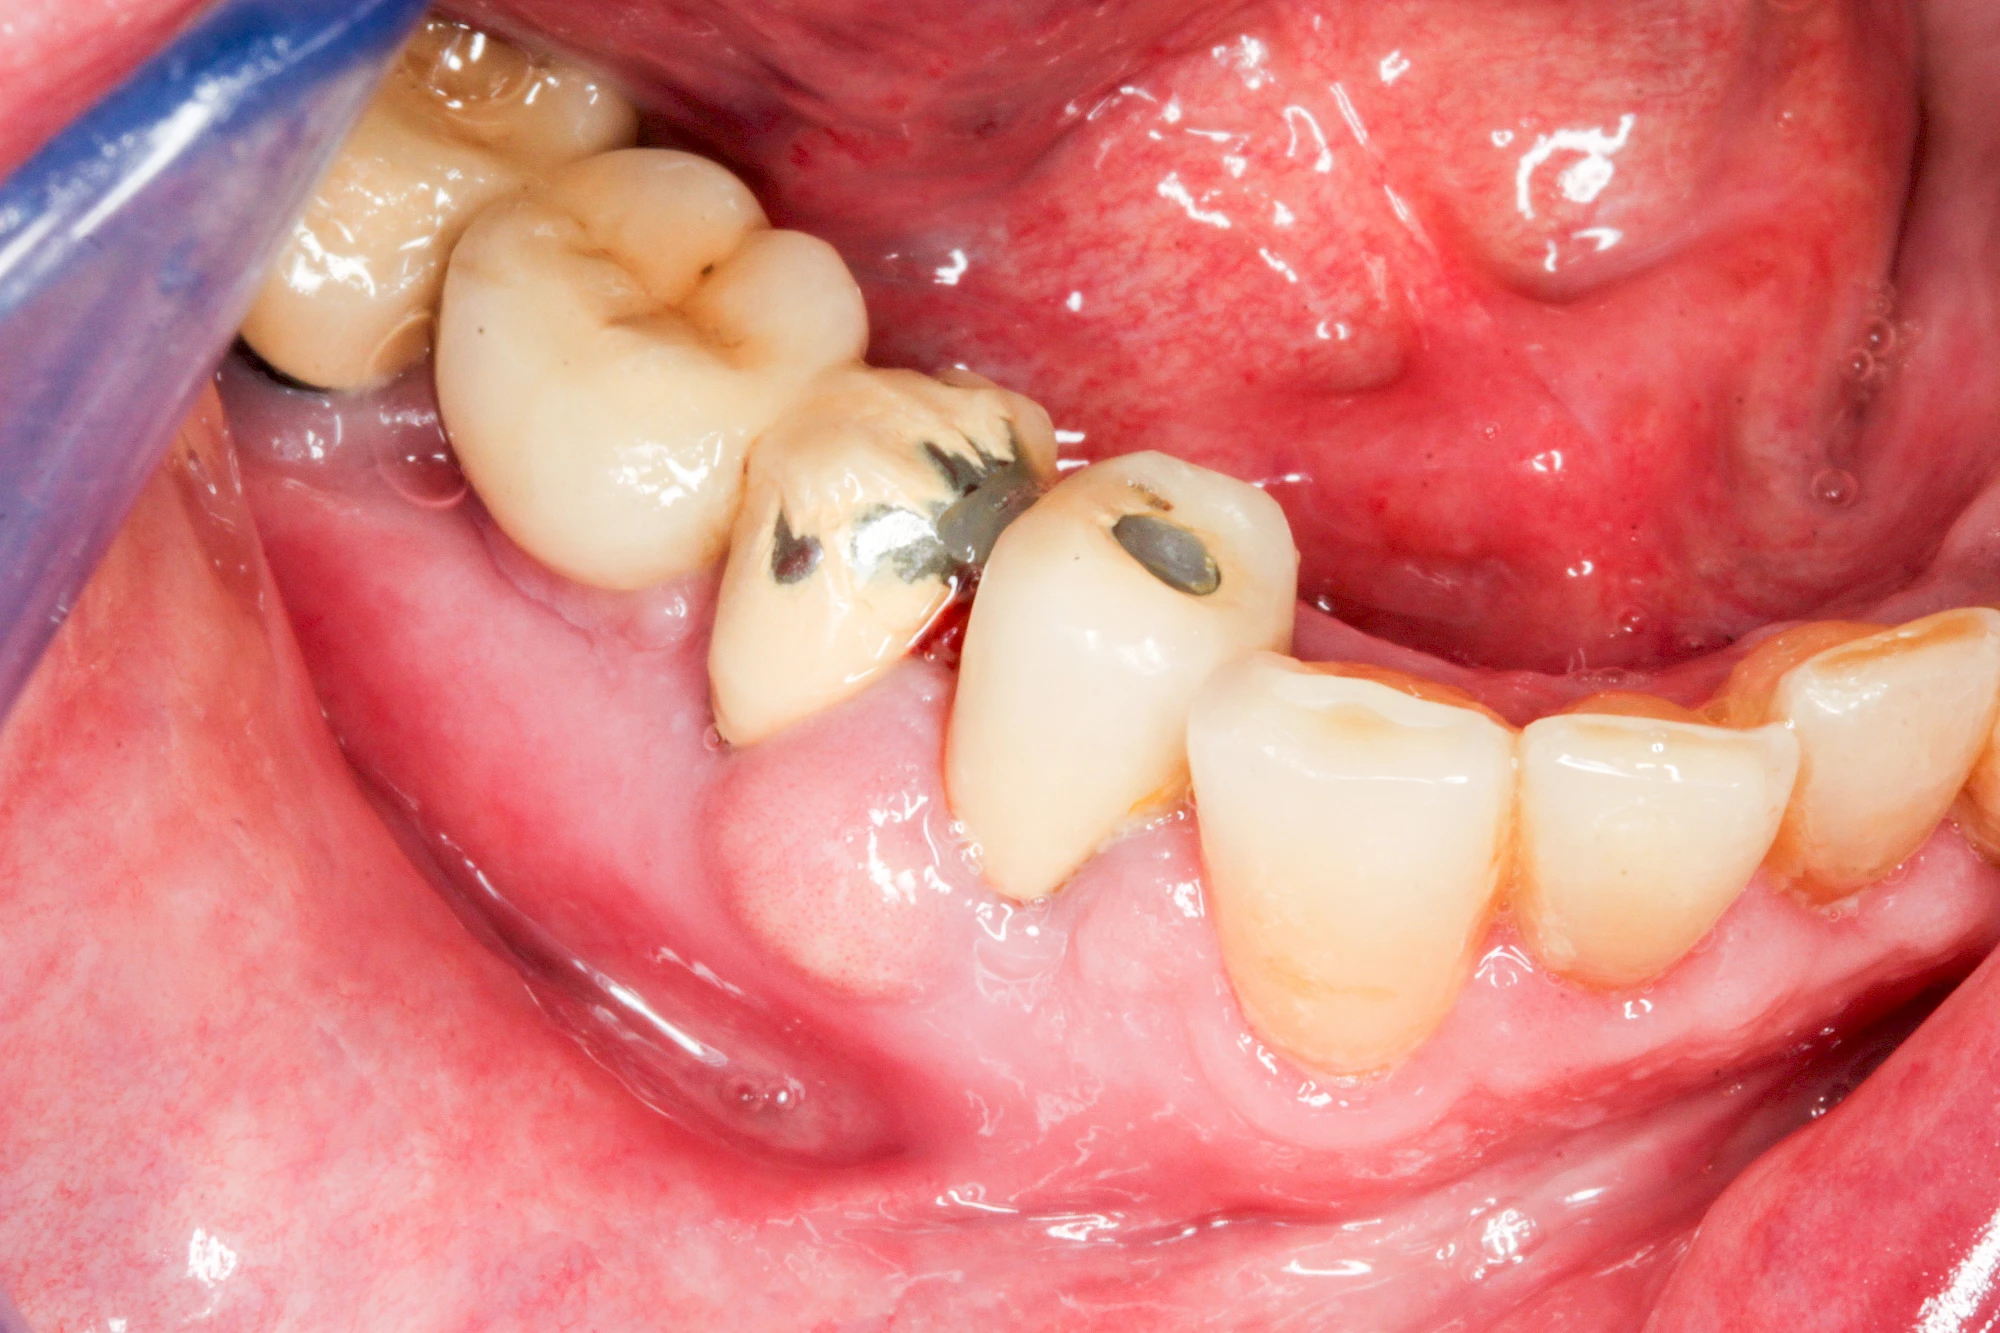

Bakterien in den Zahnbelägen greifen neben den Zähnen auch das Zahnfleisch (Gingiva) und den gesamten Zahnhalteapparat (Parodont) an. Der Körper reagiert mit einer Entzündung, sichtbar als Rötung und Schwellung. Meist blutet das Zahnfleisch z .B. beim Essen oder auch beim Putzen der Zähne.

Gingivitis & Parodontitis: Stadien

Ist zunächst nur das Zahnfleisch von der Entzündung betroffen, spricht man von Gingivitis. Später, wenn auch der Knochen um die Zähne herum entzündet ist, spricht man von einer Parodontitis. Bei der Parodontitis wird der Knochen nach und nach abgebaut und das Zahnfleisch zieht sich zurück. Die Zahnhälse und Zahnwurzeloberflächen liegen mehr und mehr frei. Die Zähne werden zunehmend lockerer und fallen schließlich aus.